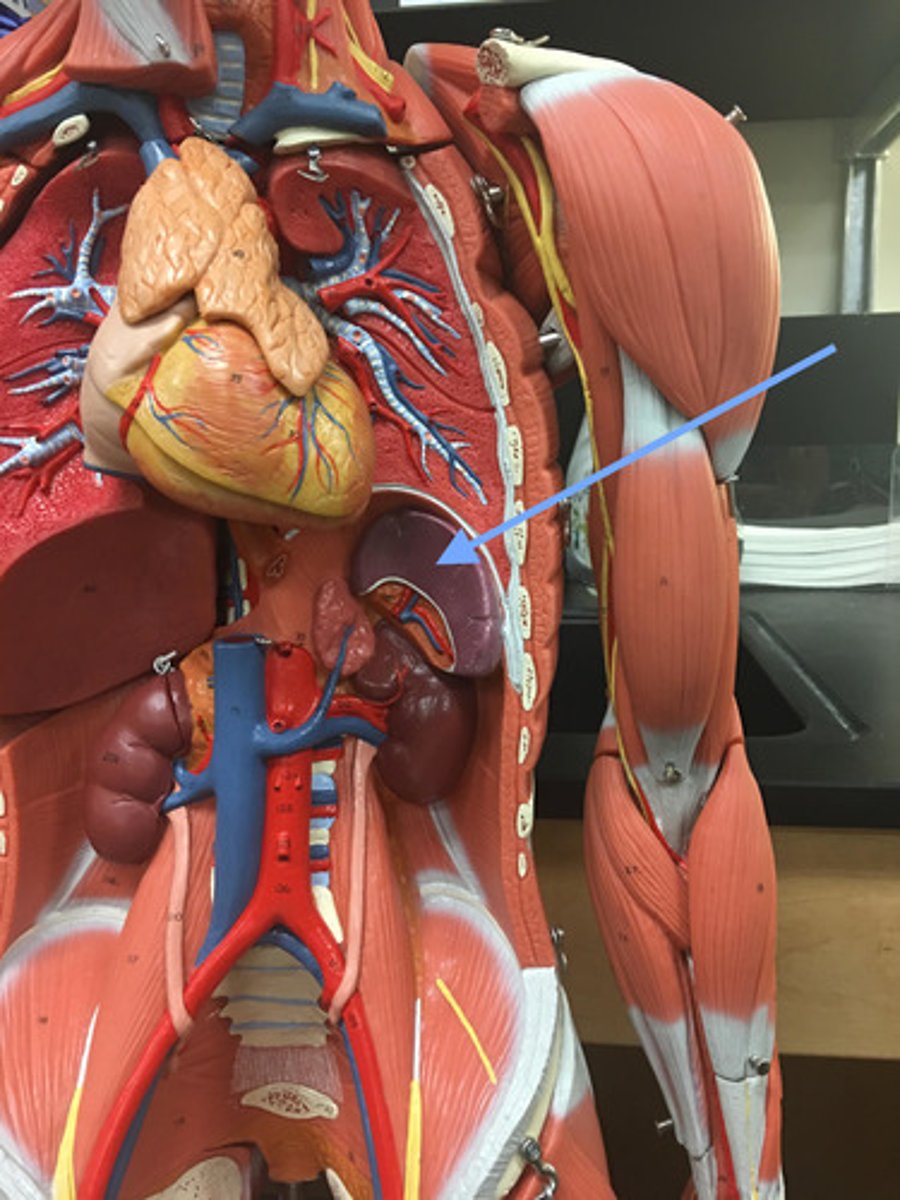

spleen

produces, stores, and eliminates blood cells

visceral surface (of spleen)

hilum (of spleen)

splenic vein